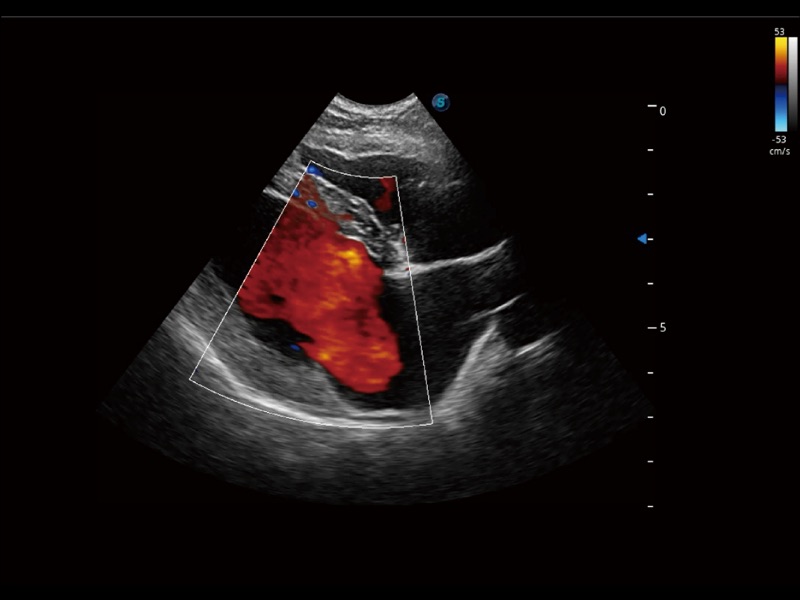

通過創(chuàng)新的 Matrix E自適應(yīng)濾波器和超長時(shí)間域算法,極大提升超低速微細(xì)血流的檢出能力,同時(shí)更精準(zhǔn)地濾除軟組織和噪聲信號,為獸用醫(yī)生提供以往無法通過常規(guī)血流獲得的疾病診斷信息。

通過色彩血流和實(shí)時(shí)寬景相結(jié)合,可觀察到完整的靜脈或動脈的血流,方便醫(yī)生檢查。實(shí)時(shí)掃查過程中,如有任何操作失誤也可以很容易地進(jìn)行回掃擦除,而不會中斷掃查。

實(shí)時(shí)用顏色表示心肌組織運(yùn)動,觀察和定量組織的運(yùn)動情況,對快速檢測與評估心肌的灌注和活性、電傳導(dǎo)及心肌收縮和舒張功能等均能提供重要的診斷信息。